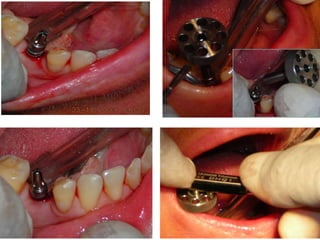

Dogmar Dasgupta,March,2009

Immediately after operation

On 11th.March,2009.

2

9

April,2012

Favorable implant-bone interface:Attributed by……. •Strictly following the basic fundamental surgical protocol for one-stage one-piece implant •Bone drilling at a very very low speed •Use of surgical tap in D1 & D2 type of bone •Immediate temporaries: out of occlusion